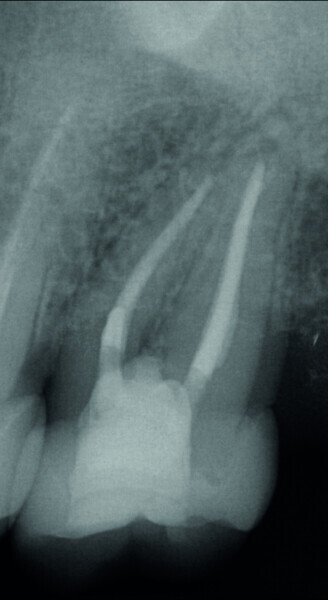

Figs. 1 et 2 : Tomodensitométrie à faisceau conique (CBCT) de la dent 27.